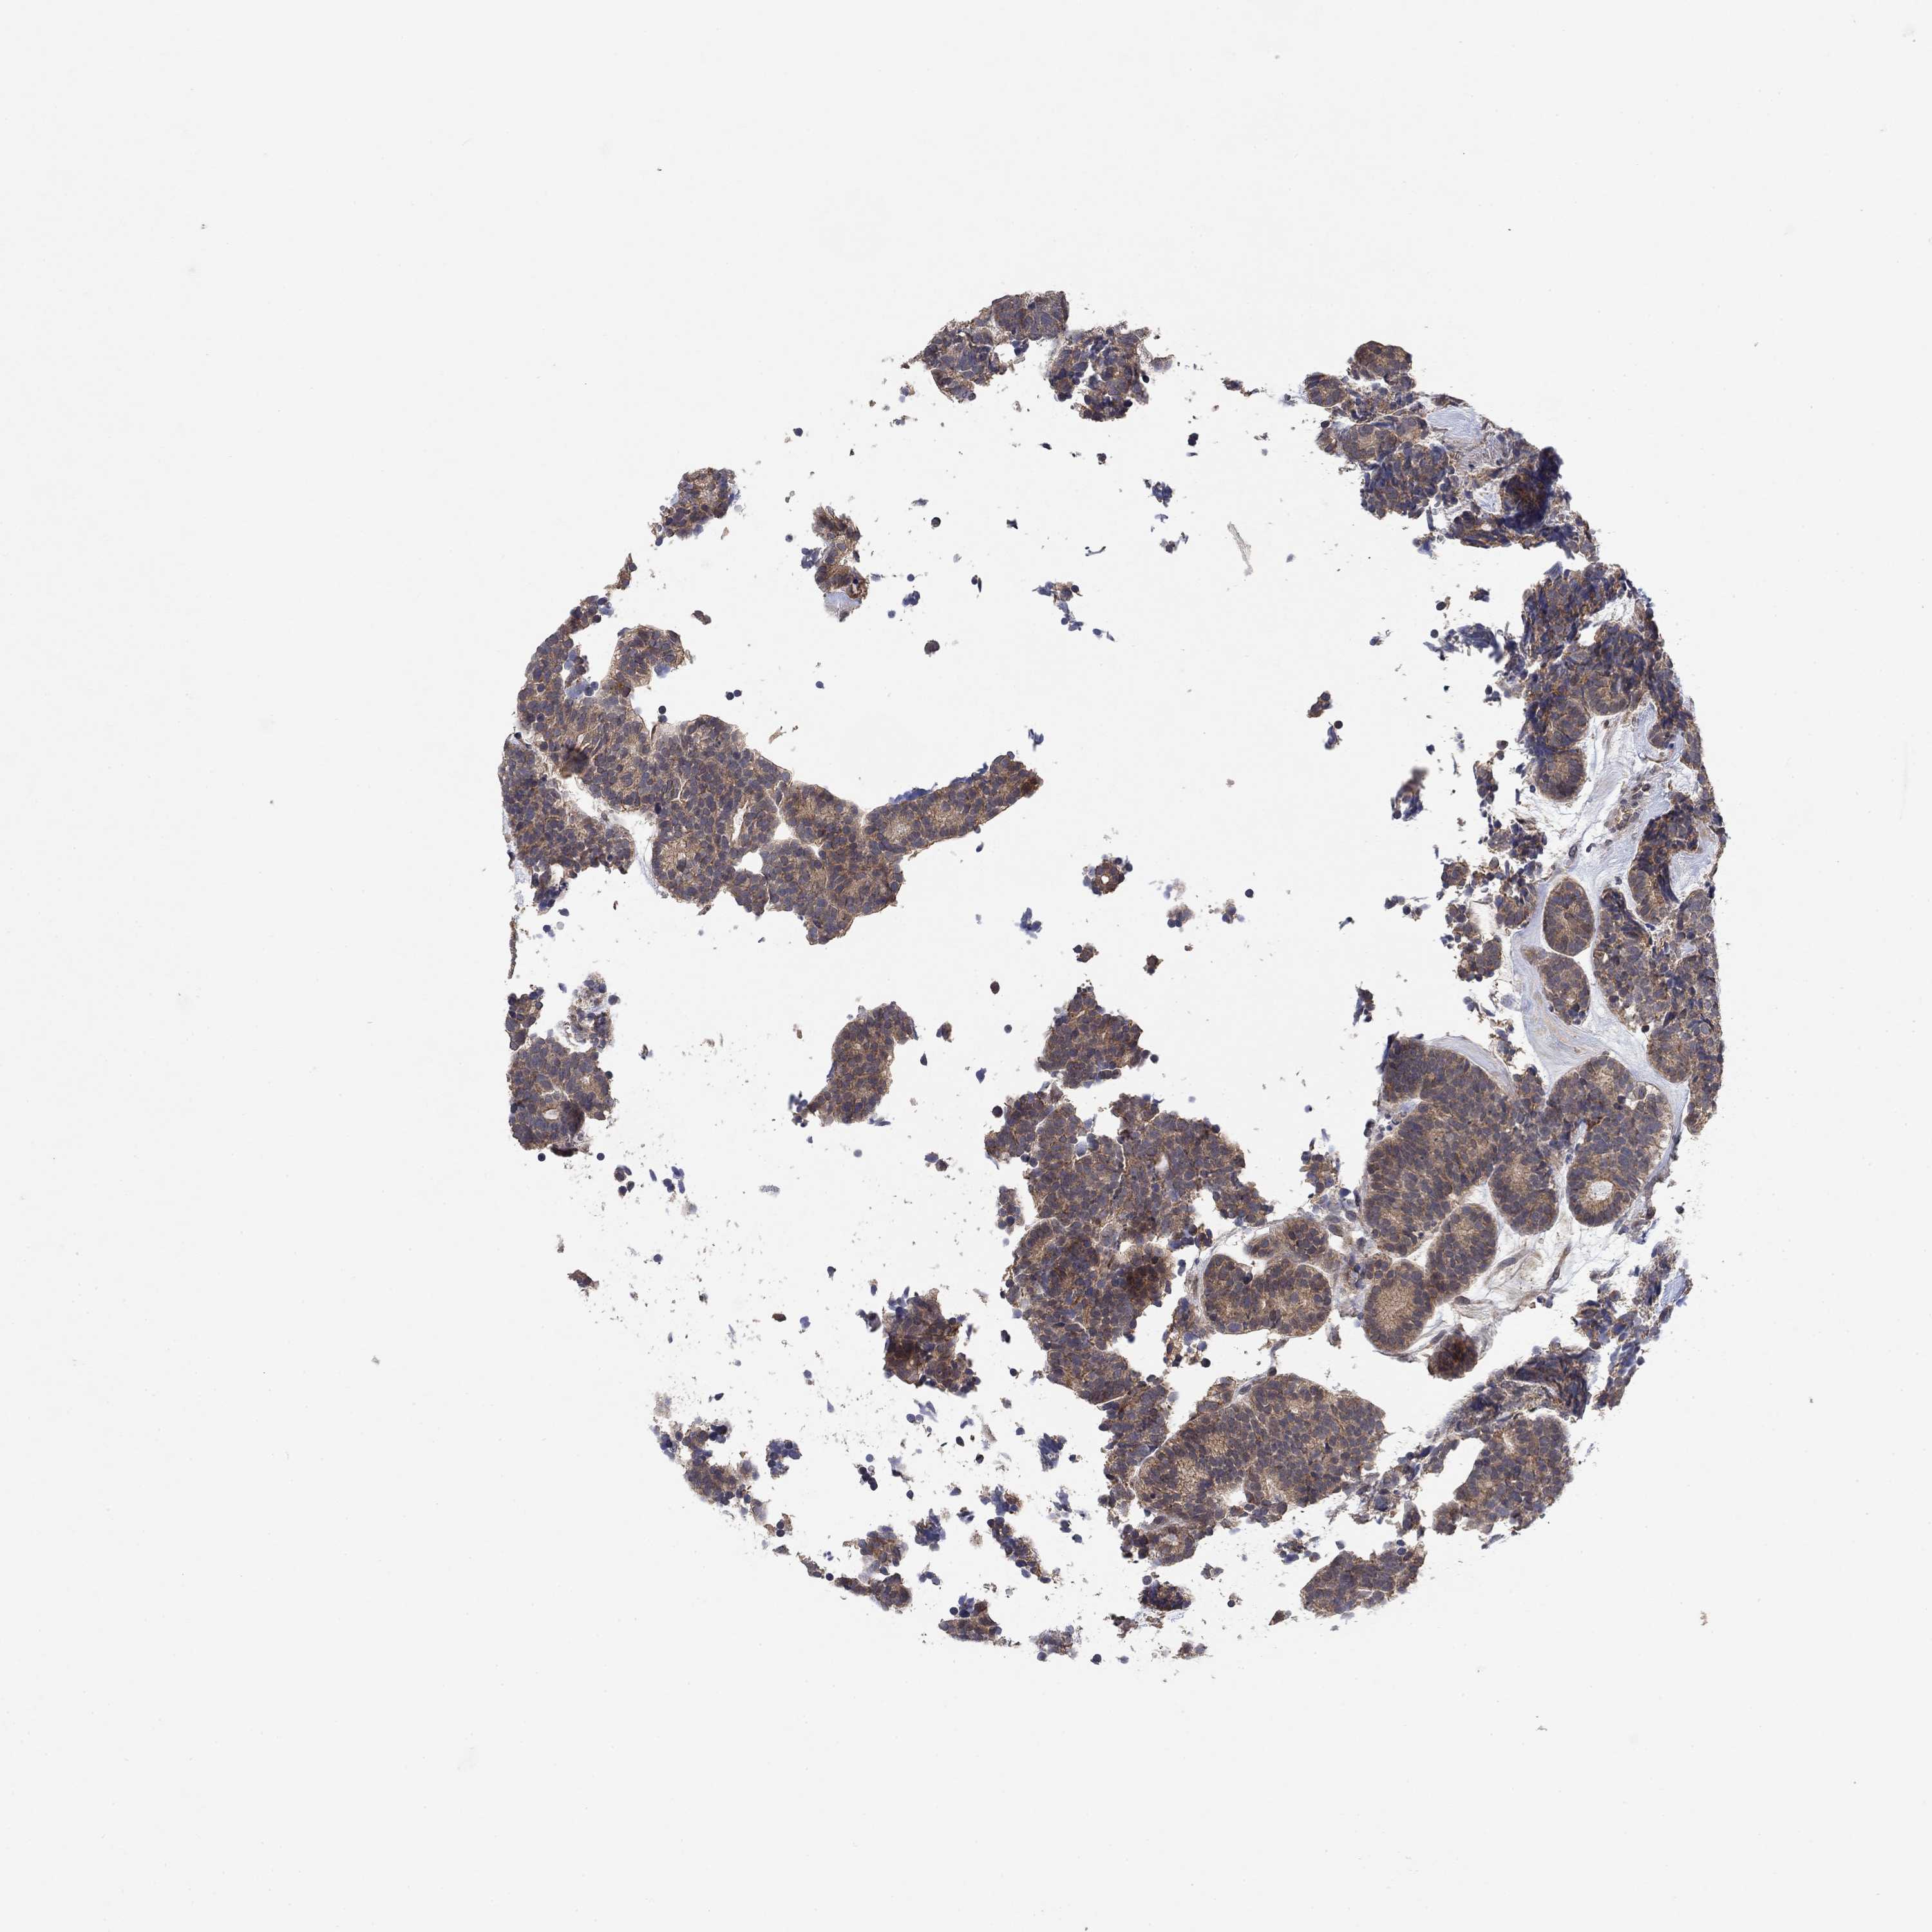

HEAD AND NECK CANCER - Protein expressioni

A mouse-over function shows sample information and annotation data. Click on an image to view it in a full screen mode. Samples can be filtered based on level of antibody staining by selecting one or several of the following categories: high, medium, low and not detected. The assay and annotation is described here.

Antibody stainingi

Antibody staining in the annotated cell types in the current human tissue is reported as not detected, low, medium, or high, based on conventional immunohistochemistry profiling in selected tissues. This score is based on the combination of the staining intensity and fraction of stained cells.

Each image is clickable and will lead to virtual microscopy that enables deeper exploration of all samples and also displays staining intensity scores, fraction scores and subcellular localization as well as patient and tissue information for each sample.

Antibody HPA078654

Staining

High

Medium

Low

Not detected

Intensity

Strong

Moderate

Weak

Negative

Quantity

>75%

75%-25%

<25%

None

Location

Nuclear

Cytoplasmic/membranous

Cytoplasmic/membranous,nuclear

Squamous cell carcinoma, NOS